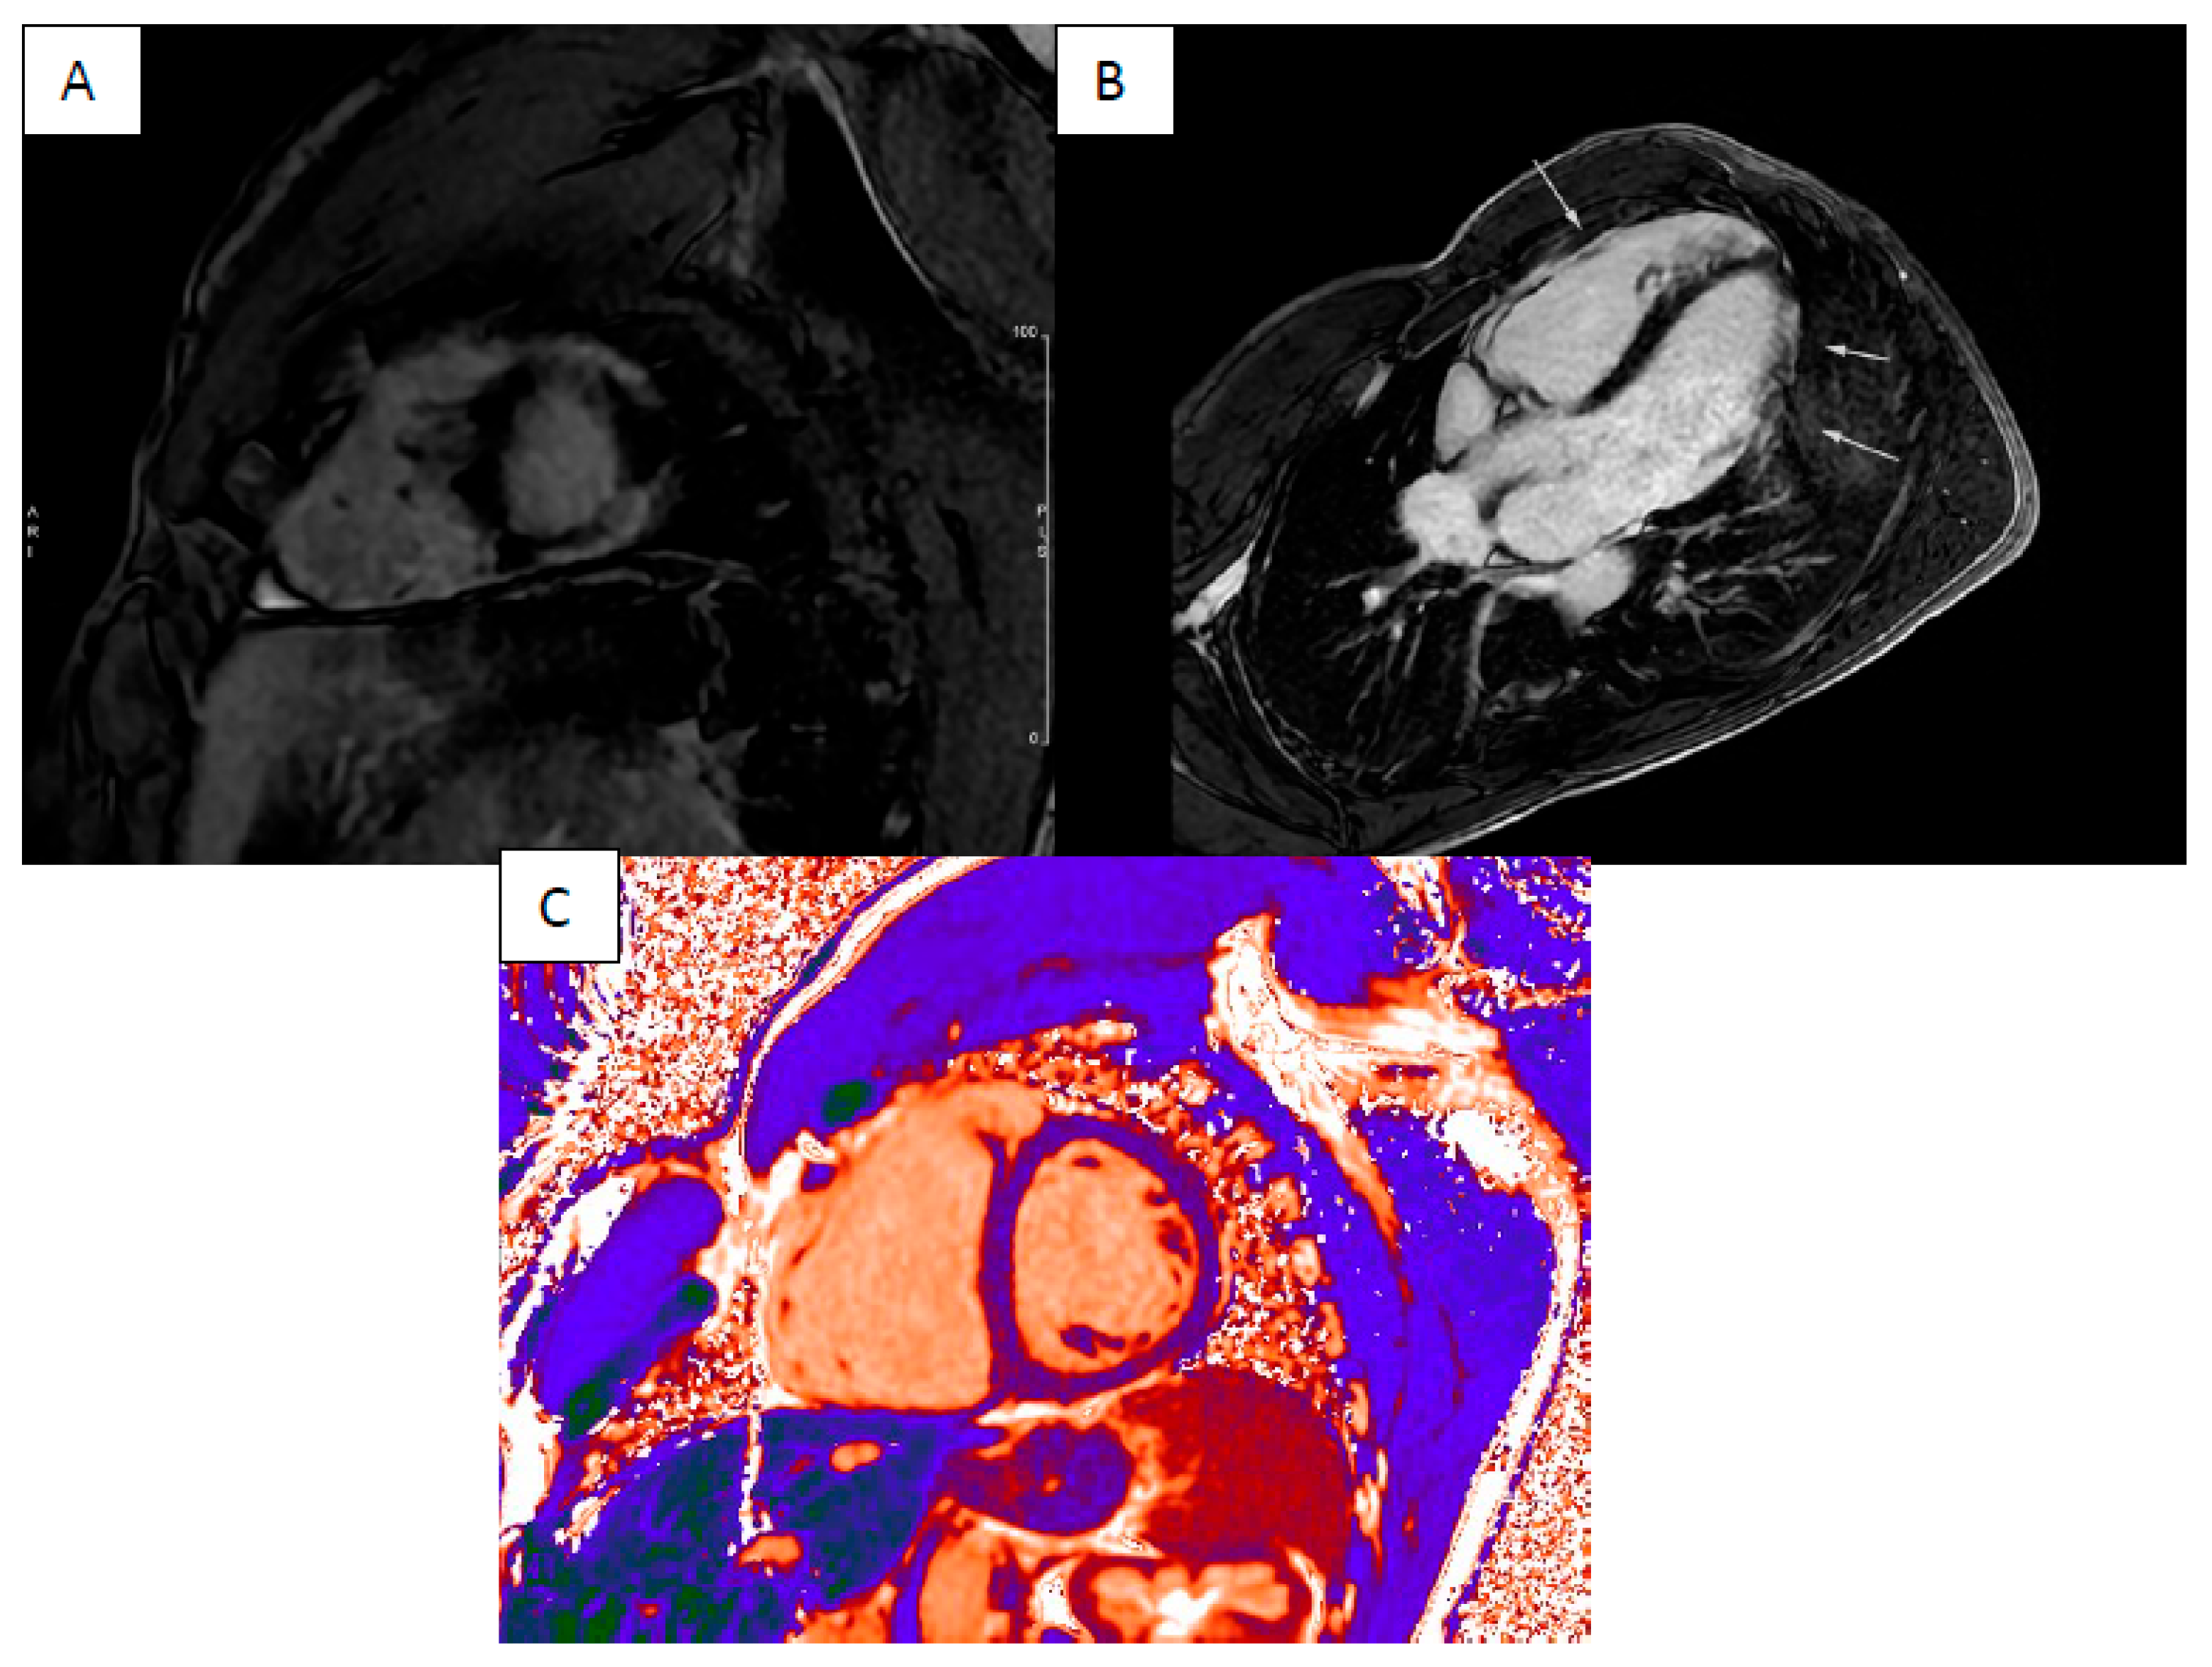

4. Cardiac Amyloidosis